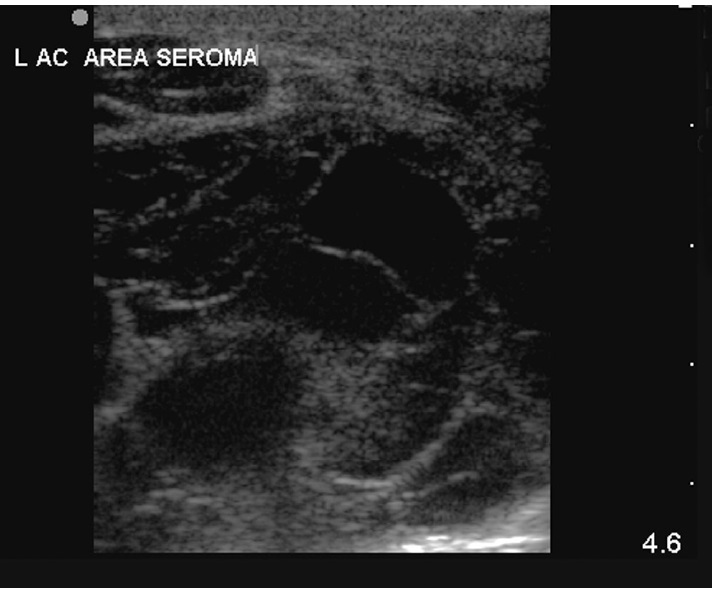

FIGURE 11 Caudolateral window – longitudinal plane: Seroma

formation – note the anechoic and hyperechoic loculated appearance.

The seroma in this area is approximately 4 × 4.5 cmin size. Cranial to

the left and skin surface at top of image

indicated